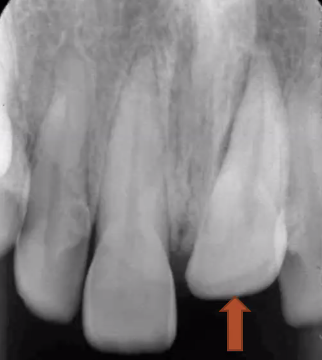

extrusion

tooth travels incisally out of socket, or partially

can mimic appearance of a periapical lesion, but crown appears supererupted

questionable prognosis → depends on how soon tooth is repositioned into socket